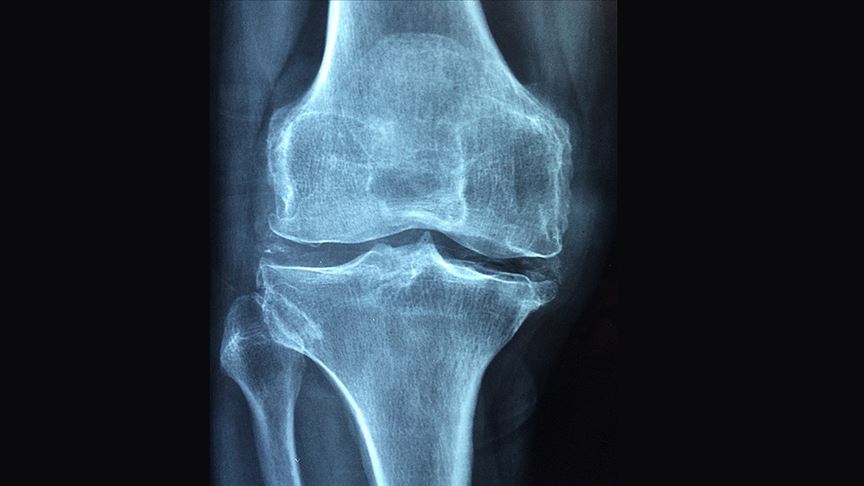

"Osteoporoz, tüm dünyada 3 kadından birini ve 50 yaş üzerindeki 5 erkekten birini etkileyen global bir sorunudur." diyen Kutsal, "Osteoporoz, tüm dünyada 200 milyon kadını etkiliyor. 60-70 yaşlarındaki kadınların üçte biri, 80 yaşlarındaki kadınların üçte ikisi bu hastalıktan etkileniyor. 50 yaşın üzerindeki kadınların yaklaşık yüzde 30'unda en az bir kırık bulunuyor. Dünyada her yıl 1,5 milyon kalça kırığı oluşuyor. Yaşlanan popülasyon nedeniyle artması bekleniyor." bilgisini verdi.

Prof. Dr. Kutsal, 2050 yılına kadar her sene global olarak 21,3 milyon kalça kırığı olacağının öngörüldüğünü ifade ederek bu nedenle osteoporoz açısından risk altında olan kişilerin mutlaka hekim tarafından değerlendirilmeleri ve korunmaya yönelik önlemlerin alınması gerektiğini vurguladı.

HÜ Tıp Fakültesi Fiziksel Tıp ve Rehabilitasyon Anabilim Dalı Öğretim Üyesi ve Türkiye Osteoporoz Derneği Genel Sekreteri Prof. Dr. Oya Özdemir de "Osteoporoz en sık görülen metabolik kemik hastalığı ve ilerleyen yaşla birlikte sıklığı artıyor. Osteoporoz, kırık olmadığı sürece ağrı yapmadığı için sessiz ve sinsi ilerleyen bir hastalık." diye konuştu.

Osteoporoza bağlı kırık gelişmesinin kişinin sağlığını olumsuz etkilediğini dile getiren Özdemir, omurga kırıklarının sırt ve bel ağrısına neden olarak hastaların yaşam kalitesini azalttığını söyledi. Özdemir, osteoporoz tanısının erken ve doğru şekilde konmasının oldukça önemli olduğunun altını çizerek menopoz sonrası dönemdeki kadınlar ve 50 yaş üzerindeki erkeklerin osteoporoz risk faktörleri açısından mutlaka incelenmesi gerektiğini vurguladı. Özdemir, "65 yaş üzeri tüm kadınlar ile 70 yaş üzeri tüm erkeklere kemik dansimetresi ile osteoporoz açısından inceleme öneriyoruz." açıklamasında bulundu.